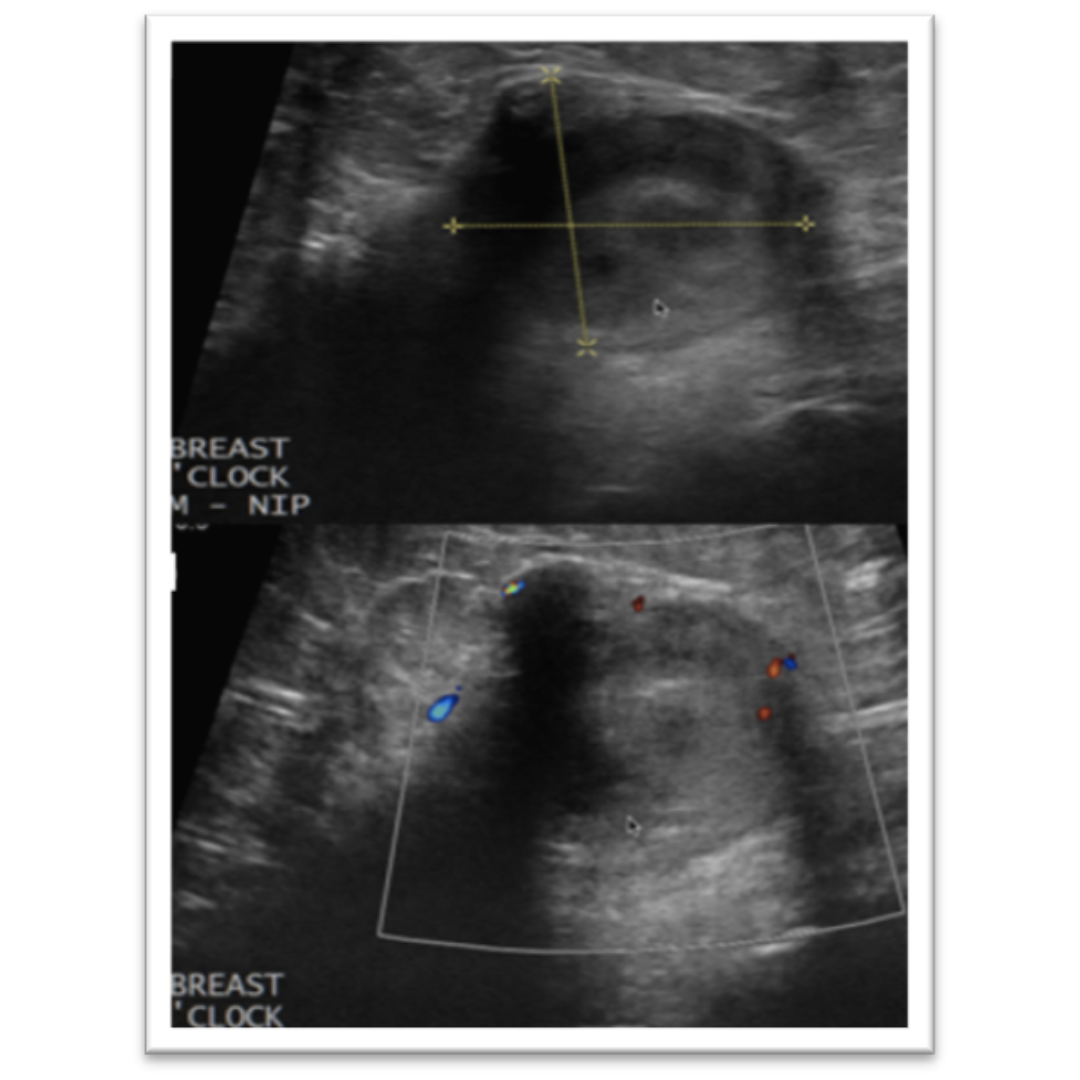

Imagen 3: Imagen nodular de morfología irregular que genera leve sombra acústica posterior, clasificada como BI-RADS 4b.